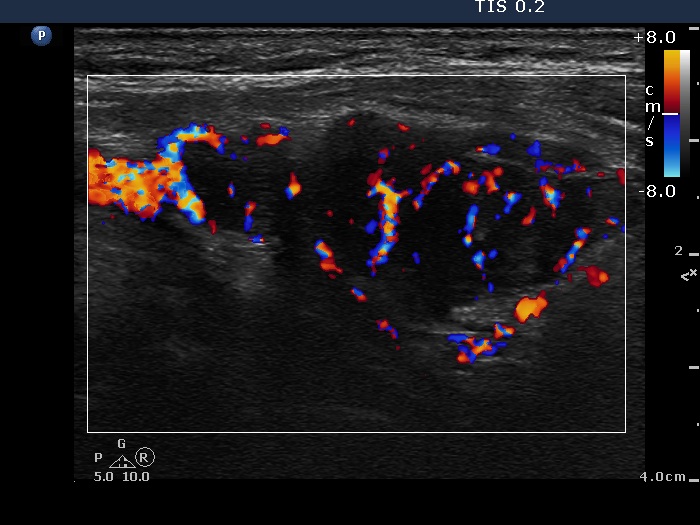

Ultrasonography: The right lobe was hypoechogenic, the left was moderately hypoechogenic. Both lobes were irregular in shape and were composed of several circumscribed areas surrounded with echonormal rim. The vascularization was significantly increased.

The sonographic pattern is specific. At first sight both lobes, particularly the right one seems to be nodular. First, the lobes are composed of a central hypoechogenic part surrounded with an echonormal rim, therefore it seems like the lobes were composed of a large hypoechogenic nodule. Second, connective tissue, perhaps a scar makes an impression in the ventral and in the dorsal part of the right and the left lobe, respectively. This makes an appearance as the lobes were composed of two nodules or one lesion with irregular lobulated and spiculated margins. In fact, the scar is responsible for the irregularities seen on the surface of the hypoechogenic mass, and regarding the hypoechogenic mass, the inclinations are the primary cause.